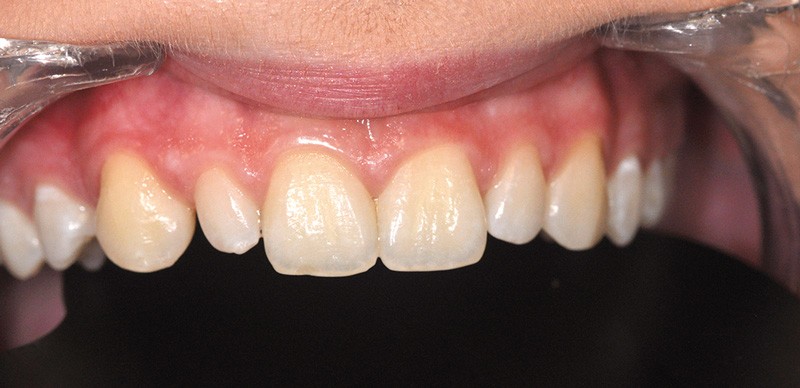

Cette étape, qui s’inscrit dans la durée, concerne la prise en charge des défauts esthétiques de grande importance, pour lesquels une prise en charge orthodontique, prothétique, implantaire se révèle nécessaire. Le rôle de l’omnipraticien est alors essentiel pour dépister et organiser le parcours de soins de l’adolescent. Ce parcours a d’ailleurs débuté dès l’enfance pour certains adolescents. Le Docteur Yves Samama a accepté de développer ces questions. Sa compétence sur le sujet permettra à chacun de mieux appréhender ces cas complexes, de la simple agénésie de l’incisive latérale (fig. 4) à la prise en charge des séquelles de fentes labiopalatines, pour lesquelles la question de la qualité et de la quantité du tissu osseux est impérative.